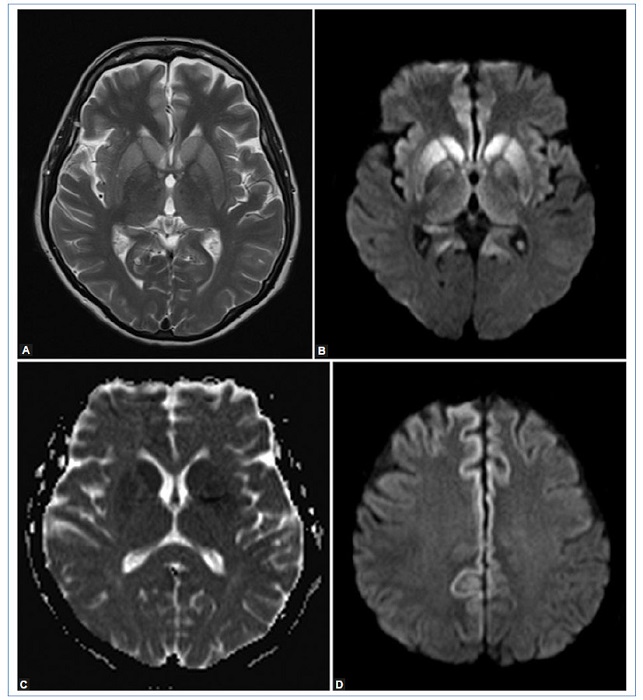

El uso de resonancia magnética (RM) en pacientes que presentan síntomas compatibles con la enfermedad aumenta la sensibilidad del diagnóstico hasta el 98%4. Los hallazgos característicos en esta consisten en hiperintensidad de la corteza cerebral y/o núcleos de la base, especialmente caudado y putamen. También se ha descrito el signo del pulvinar, que consiste en un aumento de señal simétrico en ambos núcleos pulvinares del tálamo con respecto a la corteza cerebral y la parte anterior del putamen; sin embargo, se pueden presentar falsos positivos. Otro signo descrito es el signo del “palo de hockey”, en el cual se observa un compromiso de los núcleos dorsomediales y pulvinares del tálamo3,4,5,6,7.

Se llegó al diagnóstico gracias a los hallazgos imagenológicos donde se pueden detallar los signos más comunes encontrados y descritos de la enfermedad en la literatura (hiperintensidad de los núcleos de la base, restricción a la difusión de los núcleos de la base, la corteza frontal y el giro del cíngulo y signo del “palo de hockey”) (Figs. 1,2y3), que junto con la clínica de la paciente y hallazgos en el EEG permitieron realizar el diagnóstico de ECJ.

En nuestro caso, los principales criterios diagnósticos fueron: el deterioro neurológico rápidamente progresivo, dos manifestaciones clínicas (mioclonías, compromiso de la vía piramidal), hallazgos típicos del EEG y de la RM cerebral, tratándose entonces de un caso probable de la enfermedad. Dentro de los diagnósticos diferenciales por RM están: enfermedad de Gerst mann-Sträussler-Scheinker2, encefalitis autoinmune, desmielinización osmótica, lesión cerebral hipóxica/ anóxica, encefalopatía hepática, encefalopatía hipoglucémica y enfermedad mitocondrial.